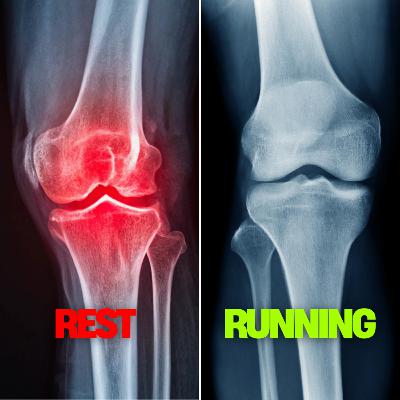

If you’re an injured runner we can help you get back to running pain-free.Click the link to book a free call with ushttps://matthewboydphysio.com/booking/Running Fundamentals Coursehttps://matthewboydphysio.com/running-fundamentals-course/Instagramhttps://www.instagram.com/matthewboydphysio/Related YouTube VideoDoes More Running Cause More ArthritisPainless Knee ArthritisSummaryIn this episode, Matthew Boyd discusses the relationship between running and knee arthritis, debunking the myth that running exacerbates arthritis. He emphasizes the importance of exercise in managing arthritis pain and preventing further deterioration. Boyd shares a success story of a runner who, despite having arthritis, was able to train for and complete a marathon through a structured rehabilitation program that included strength training and adaptive running techniques. He concludes that rest is not the solution for arthritis; rather, building strength and maintaining activity are crucial for managing symptoms.TakeawaysRest from running makes knee arthritis worse.People who run with arthritis experience less pain.Exercise is important to stop the progression of arthritis.Being sedentary leads to worse arthritic symptoms.Weight gain is associated with worsening arthritis.Running keeps you lean and healthy.Resting makes knees weaker and less resilient.A structured training program can help manage pain.Strength training can offload stress from the knees.Healthier individuals tend to have healthier knees.

If you’re an injured runner we can help you get back to running pain-free.Click the link to book a free call with ushttps://matthewboydphysio.com/booking/Running Fundamentals Coursehttps://matthewboydphysio.com/running-fundamentals-course/Instagramhttps://www.instagram.com/matthewboydphysio/SummaryThis episode delves into the complexities of arthritic pain in runners, exploring its symptoms, variations in severity, and the importance of maintaining an active lifestyle. Matthew Boyd emphasizes the need for runners to understand their condition, manage pain effectively, and seek professional guidance to continue running safely and healthily.TakeawaysArthritic pain in runners can vary significantly in severity.Understanding the nature of arthritic pain is crucial for management.Staying active is essential for joint health in arthritis.Strength training is vital for reducing pain and improving function.Running can serve as a form of rehabilitation for arthritic joints.Proper biomechanics can help reduce stress on affected joints.Monitoring pain levels is important for safe training.Professional guidance can enhance recovery and performance.It's important to explore all options before considering surgery.Maintaining a healthy lifestyle supports joint health.